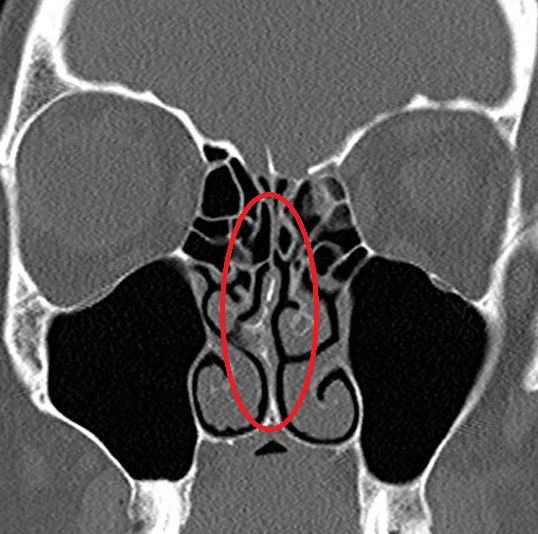

Lean forward slightly, close one nostril with a finger, and angle the nozzle slightly outward, toward the outer corner of the eye, not straight up the middle.

This prevents the spray hitting the nasal septum (the middle wall), which can cause irritation or nosebleeds.

🚫 Pointing the nozzle incorrectly: Always aim slightly outward, not toward the septum.

What is the correct way to aim a nasal spray?

Always aim the nozzle slightly outward, towards the outer corner of the eye on the same side — not straight up the middle.